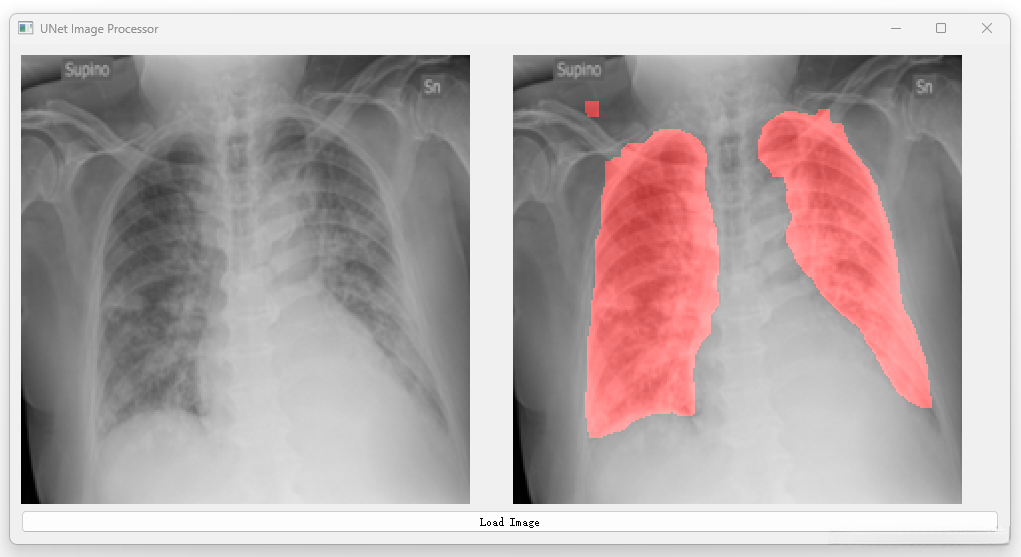

开发一种高效且可靠的U-Net网络架构以解决肺部CT图像分割任务。 通过优化算法设计提升图像分割精度的同时有效抑制噪声污染和伪影生成。 实现对肺部各区域(如支气管血管网等)的精细解析确保诊断准确性。 设计一个操作便捷的人机交互界面便于临床医师进行影像分析及评估。

将经过优化的Unet架构应用于实际临床CT扫描数据中进行分割操作,并实现精准识别目标区域边界的目标达成。

对分割结果实施后端质量控制流程:包括噪声去除、空洞填充等步骤确保最终输出满足临床应用需求的标准要求并提高准确性水平。

深度学习之基于Unet肺部CT图像分割项目

三、系统